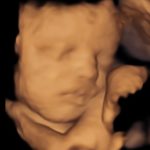

4D/5D/HD Ultrasound Gallery

Gallery